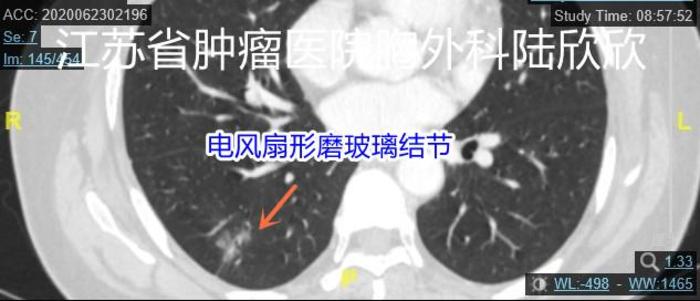

十、电风扇形磨玻璃结节

这个磨玻璃结节形状像电风扇的三个风扇叶子。病理是浸润性腺癌。